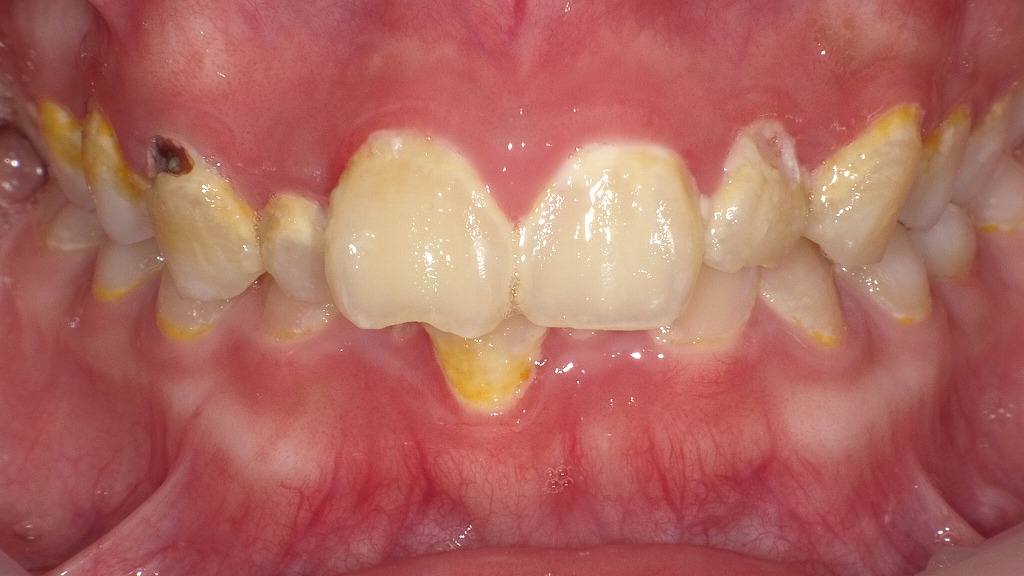

この画像では、以下のような状態が確認されます。

🦷全体的な所見

- **歯の表面や歯頚部(歯と歯ぐきの境目)に黄色いプラーク(歯垢)**が多く付着しています。

→ プラークは細菌のかたまりで、糖分を栄養にして酸を産生します。

→ 酸によって歯の表面(エナメル質)が溶け出し、虫歯の原因になります。

⚠️虫歯(う蝕)の所見

- 左上犬歯(画像左側の尖った歯)付近の歯頚部にC2程度の虫歯が見られます。

→ エナメル質を越えて象牙質に達しており、治療が必要な状態です。

→ 黒褐色に変色し、表面の凹みが認められます。

🧫プラークと細菌活動

- 黄色いプラークは、成熟した細菌バイオフィルムの特徴を示しています。

→ 細菌が活発に活動し、酸を産生していると考えられます。

→ 特に歯頚部や歯間部に多く付着しており、ブラッシング不足や磨き残しが原因と推測されます。

🪥治療とケアの提案

- プロフェッショナルクリーニング(PMTCまたはスケーリング)

→ プラーク・歯石を除去して、再付着を防ぐ。 - C2虫歯の充填治療

→ コンポジットレジンやインレーによる修復を検討。 - ブラッシング指導とプラーク染め出し

→ 毎日のセルフケアでプラークの取り残しを防ぐ。 - フッ素塗布またはMIペースト使用

→ 初期脱灰部の再石灰化を促進。 - 食生活指導(糖の摂取頻度減少)

→ 細菌の酸産生活動を抑制。